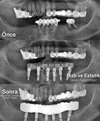

Implant tedavisi